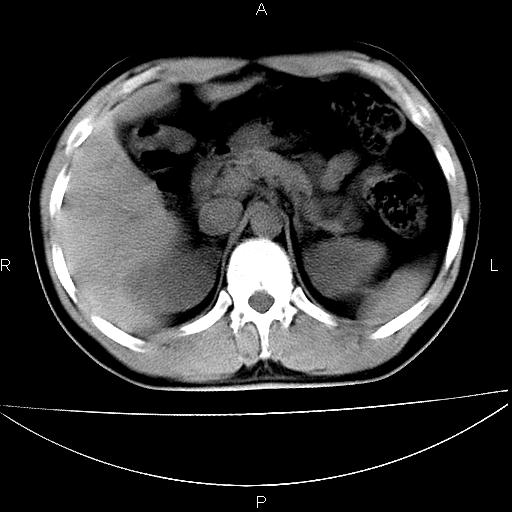

男 25岁 自述 尿频尿急,排尿困难20多天.无腰痛, b超说左肾盂轻度积水,左输尿管上端扩张.未见结石影. ct我看双侧肾盂轻度积水,双输尿管上端都扩张,大家看看能看见结石吗?

双输尿管扩张下端未见高密度结石和输尿管晕轮征,不好说是结石.增强后如何?

双侧输尿管上端扩张,未见明确结石,可进一步ivp检查。

考虑肾外肾盂 前列腺轻度肿大 密度欠均 考虑炎性改变